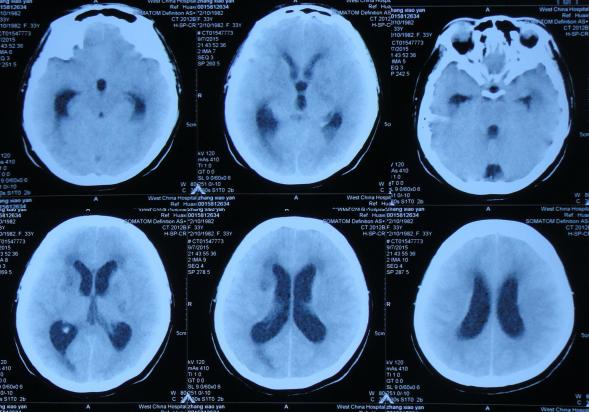

2016年6月3日住入李小勇脑脊液中心,入院时:卧床,反应慢,表情淡漠,言语迟钝(问答无反应),吞咽困难,只能鼻饲流食,头部有多处手术疤痕,右下肢自主活动差,但刺激后能动(图-25);入院第2天即2016年6月5日,头部CT示脑积水,脑室粘连,脑萎缩(图-26)。

图-26:2016年6月5日头部CT入院时